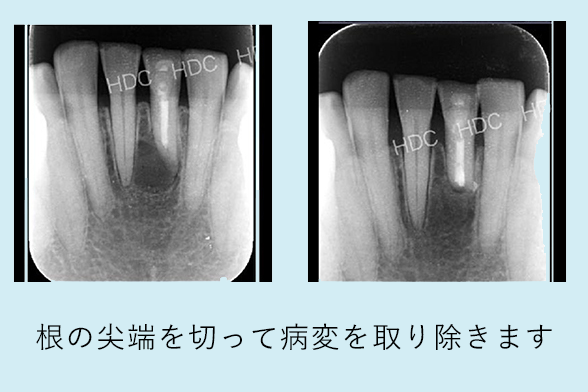

名古屋市名東区の自費の根管治療

根管治療だけでは治らない歯の根の先の病気を治療するために、歯ぐきを切開し、歯根の先端を外科的に切除して薬をつめる治療法です。